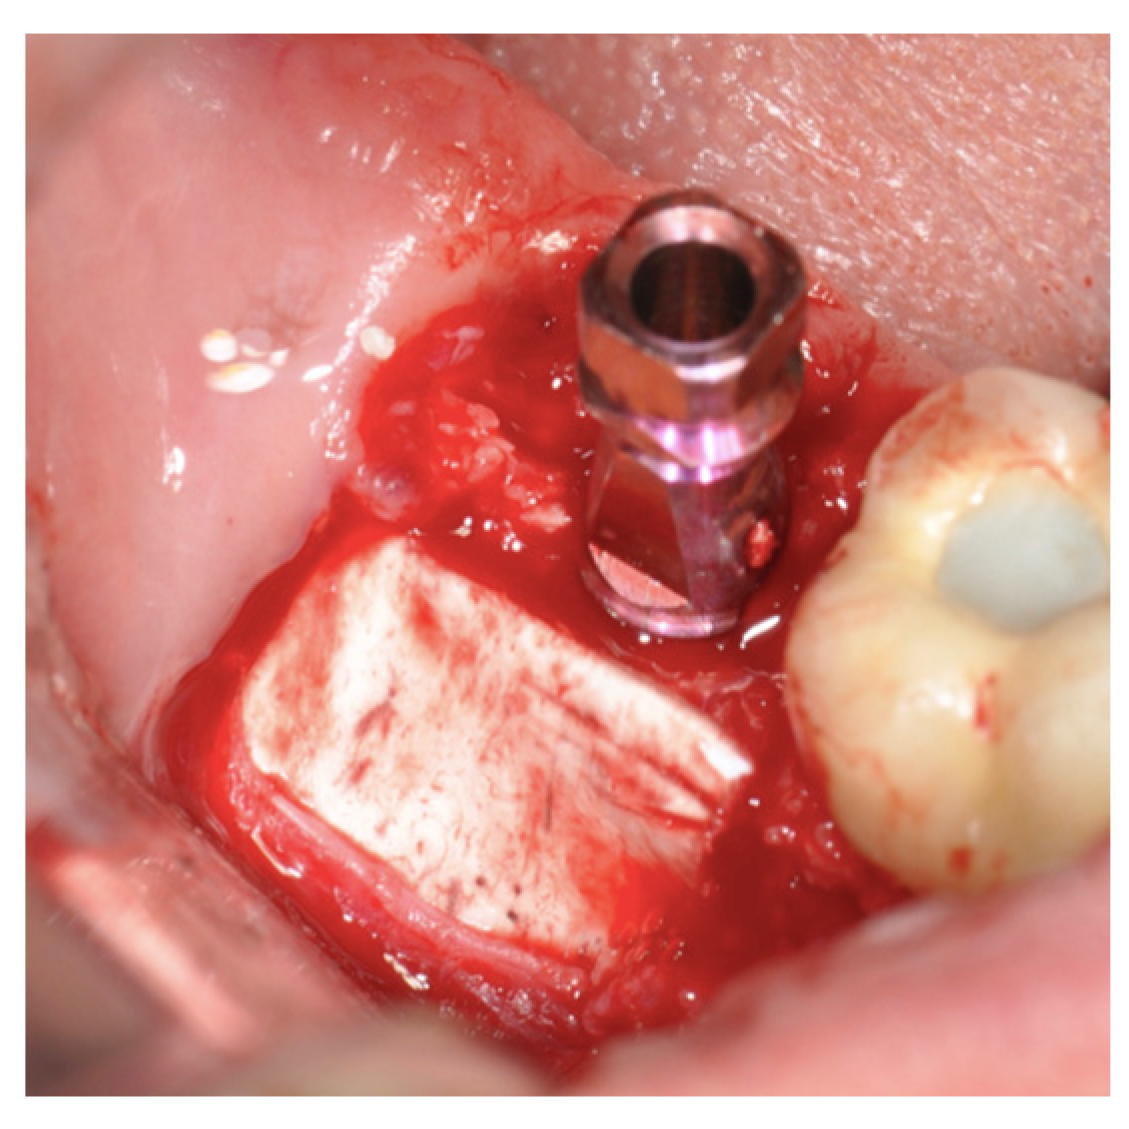

2.2. Surgical Technique